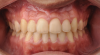

Fig 13. Dental views of the patient 3 years after surgical-orthodontic correction; right lateral view (Fig 13), frontal view (Fig 14), and left lateral view (Fig 15).

Figure 13

Fig 14. Dental views of the patient 3 years after surgical-orthodontic correction; right lateral view (Fig 13), frontal view (Fig 14), and left lateral view (Fig 15).

Figure 14

Fig 15. Dental views of the patient 3 years after surgical-orthodontic correction; right lateral view (Fig 13), frontal view (Fig 14), and left lateral view (Fig 15).

Figure 15